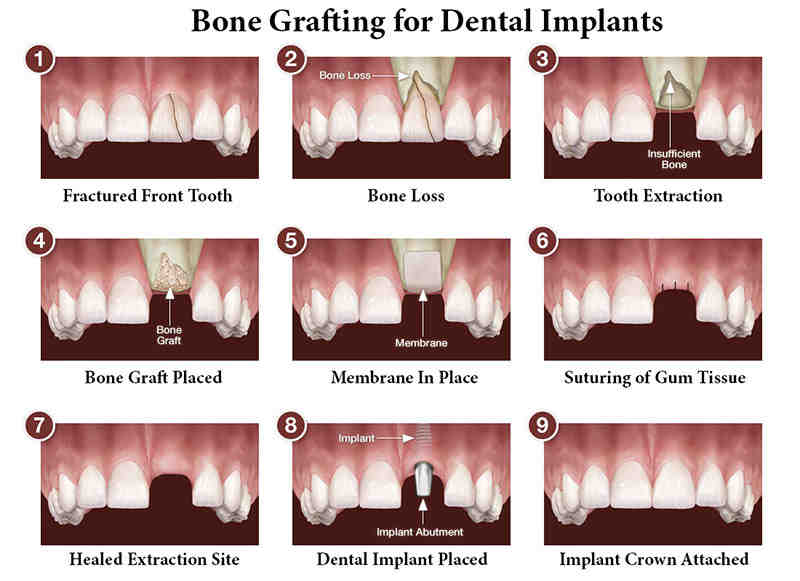

Is dental bone grafting dangerous?

Bone grafting is generally safe, but it has some rare dangers. There is also a risk that your bone will not heal even with the bone graft. See the article : Titanium Dental Implant. Many of your specific risks will vary depending on the exact cause of the bone graft.

Do they put you to sleep for dental bone graft?

Usually, an oral surgeon uses local anesthesia or IV sedation during surgery. On the same subject : Brightside dental what do they charge for a dental implant ?. The oral surgeon starts by removing the bone from another part of the body, such as the hip or the back of the jaw.

What can I expect after dental bone graft?

After a dental bone transplant, you can expect some pain or discomfort. Your dentist will probably prescribe antibiotics and painkillers to help you feel more comfortable during recovery and to prevent infection.

Do dental implants always require bone grafts?

Bone grafting is not always necessary for the placement of dental implants, but in cases where this procedure is indicated, it can help to significantly improve the patient’s chances of good treatment results. Only your surgeon can determine the need for a bone graft, often using special imaging technology.

How long does a dental bone graft take?

Bone grafting procedures tend to take somewhere between 20 minutes and 90 minutes to complete. It will depend on the location of the transplant, how much bone needs to be inoculated and whether other necessary dental procedures need to be done first or not, such as tooth extraction.